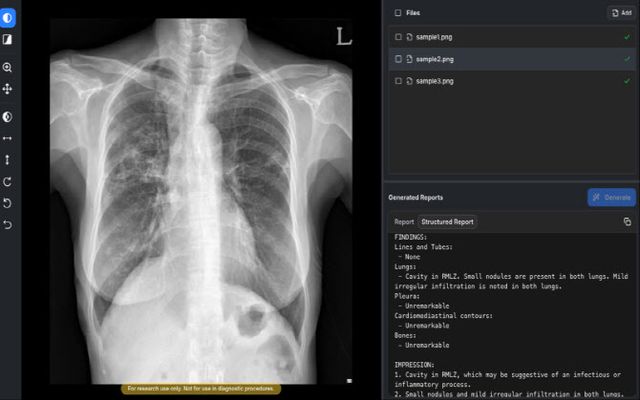

기존 판독 보조 AI가 병변 위치나 이상 유무를 표시하는 데 그쳤다면, AIRead-CXR은 한 단계 더 나아가 텍스트 형태의 예비소견서를 직접 생성하는 것이 특징이다.

식약처에 따르면 이 제품은 흉수, 기흉, 폐부종, 폐결절, 심장비대, 활동성 결핵, 늑골 골절, 쇄골 골절 등 57종을 판독 대상으로 삼고 있다. 숙련된 영상의학과 전문의 5명이 참여한 비교 평가에서도 실제 임상 판독과 유사한 수준의 성능이 확인됐다는 게 회사 측 설명이다.